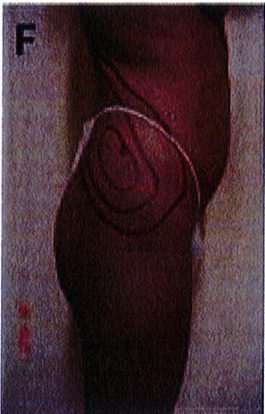

Theo kinh nghiệm của tác giả, nhiễm trùng lớp bề mặt và hoặc bục chỉ vết mổ là hai biến chứng thường gặp nhất (Hình 6). Nếu bục chỉ ở các lớp bề mặt thì có thể chăm sóc tại chỗ, làm sạch vết mổ và chờ liền. Còn trong trường hợp nặng, có thể thấy các tổ chức sâu phía bên dưới thì cần chăm sóc đặc biệt, thay băng và làm sạch vết mổ thường xuyên cho tới khi thấy được mô hạt sạch trên vết mố. Sau đó nên đóng vết mổ theo hai kỳ, kỳ đầu là lớp sâu, kỳ sau là lớp nông và cách nhau môt tuần.

Hình. 6. Bục chỉ vết mô